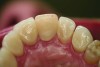

Figure 5 and Figure 6. All-ceramic restorations (Figure 5) and opposing dentition wear (Figure 6) produced by all-ceramic feldspathic restorations.

Figure 5

Ceramic hardness ranges from 481 Hv to 647 Hv for veneering porcelain to 1,354 Hv to 1,378 Hv for zirconia.22,23 Since enamel has a hardness of 300 Hv to 500 Hv,24 concerns have been raised that ceramic restorations will cause destructive wear to opposing teeth. Studies measuring the wear of enamel opposing zirconia and lithium disilicate, however, have proven that these high-strength ceramics produce less opposing enamel wear than veneering ceramics or enamel itself.25-28 For example, in-vitro volumetric enamel wear from 400,000 chewing cycles measured 0.33 mm3 against zirconia, 0.36 mm3 against lithium disilicate, 2.15 mm3 against veneering porcelain, and 0.45 mm3 against enamel.26 When veneering porcelains are worn against enamel, the porcelain surface becomes rough from microfractures of the material. The rough surface of the porcelain is abrasive to the enamel and results in opposing enamel wear (Figure 5 and Figure 6).29 High-strength ceramics do not fracture when worn against enamel; therefore, their surface remains smooth and wear-friendly to opposing enamel. Additionally, high-strength ceramics experience very little wear on their own surface. The recent trend in full-contour monolithic lithium-disilicate and zirconia crowns is partially justified by the wear-compatibility between these ceramics and opposing enamel.